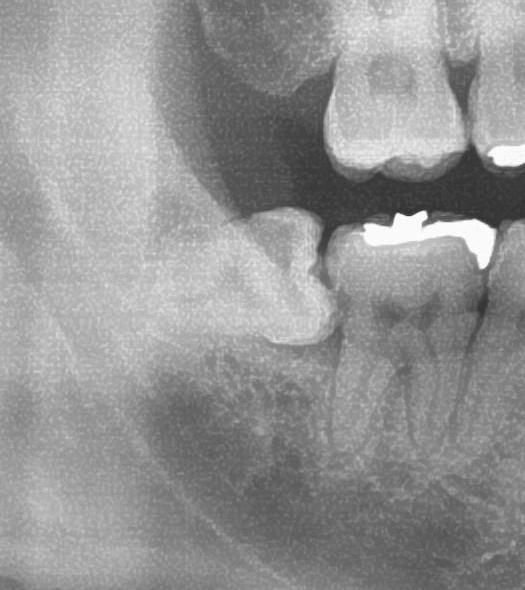

まずお口の中を見てみると、右下の親知らずは頭の一部分が少し見えている状態でした。

次にパノラマ写真を撮影してみると、右下の親知らずは手前の歯の歯を押すように斜めに生えているのが確認できました。